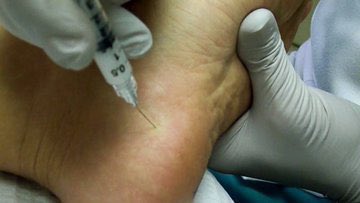

♦️الحقن الكورتيزون الموضعية تخفف حدة الالتهاب ومن ثم تقلل الالم

♦️في بعض الحالات التي لا تستجيب لطرق العلاج المختلفة،

يلجأ الى التدخل الجراحي